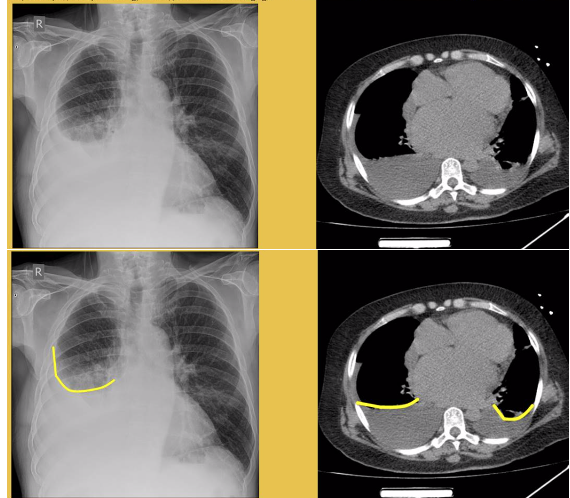

radiological findings: CXR and CT

Meniscus showing fluid in the pleural cavity (right base)